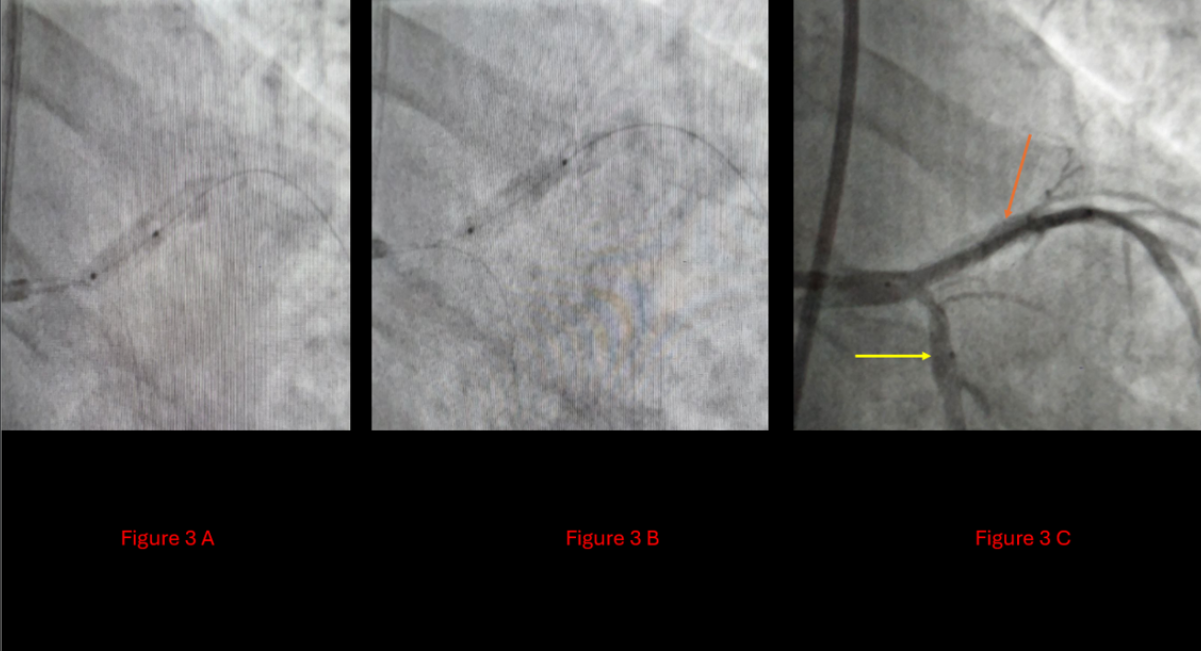

In the absence of other viable options, intravascular lithotripsy (IVL) was employed—a challenging and resource-intensive choice, particularly in a low-income setting such as Jordan. Shockwave Lithotripsy was applied with 70 pulses to the LAD and 10 pulses to the Cx. This allowed successful modification of the calcified lesions, creating a safe environment for definitive bifurcation intervention. A Double-Kiss Crush (DK-Crush) stenting technique was then performed for the LM-LAD-Cx bifurcation, employing a 1:1:1 Medina classification strategy (Figure 3). A new drug-eluting stent was deployed in the LAD, with final angiography showing fully patent three-vessel flow (Figure 4).

Figure 3A: Insertion of the shockwave balloon

3B: Postshock wave non-compliant balloon

3C: Orange arrow: LAD post shockwave, Yellow arrow: Cx post shockwave